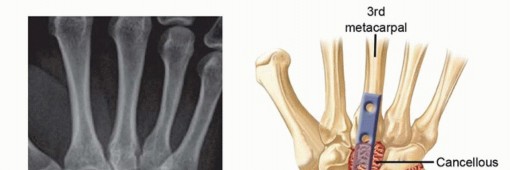

15 MIN READ Surgical Management of Traumatic Conditions of the Elbow: Interposition Arthroplasty يناير 2023 Read More